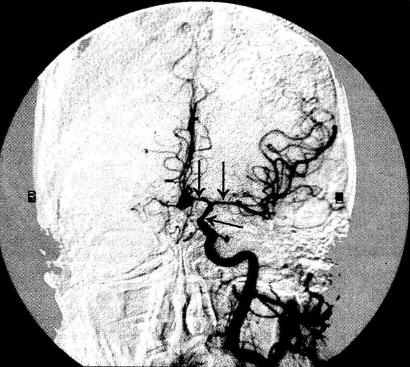

Церебральный ангиоспазм наблюдается часто при атеросклерозе сосудов головного мозга и лежит в основе патогенеза ишемического варианта церебрального криза у больных гипертонической болезнью. Отличительными симптомами этого варианта от других острых церебральных ангиодистоний являются очаговые неврологические нарушения, характерные для зоны ишемии головного мозга, соответствующей бассейну спазмированной артерии ( Гипертонические кризы). У больных атеросклерозом головного мозга такие нарушения могут быть обусловлены не ангиоспазма, а механизмами так называемой цереброваскулярной недостаточности - снижением кровотока в зоне расположения атеросклеротической бляшки при падении АД (например, ортостатическом), расстройствах сердечной деятельности. Наличие последних, регистрация сниженного АД, при ортостатических пробах, помогает дифференциальному диагнозу.

Патогенез ангиоспазма изучен недостаточно, для артерий разных сосудистых регионов он не идентичен, но общим для механизма развития любого ангиоспазма является расстройство функции мембран гладкомышечных клеток сосуда, состоящее в нарушении обменного транспорта через мембраны ионов кальция, натрия, калия, что нарушает нормальное чередование фаз мышечного сокращения и расслабления. Ускоренная и усиленная деполяризация мембран, повышенный приток в клетки свободных ионов кальция способствуют развитию интенсивного мышечною сокращения, а задержка процессов реполяризации мембран (в норме предшествующей расслаблению мышцы) обусловливает длительное пребывание артериальной стенки в сокращенном состоянии. К таким нарушениям могут привести расстройства иннервации сосудистых стенок, дисбаланс в продукции и разрушении гуморальных регуляторов сосудистого тонуса, а также повышенная чувствительность рецепторов сосудистой стенки к нормальным вазоконстрикторным влияниям, что нередко обусловлено локальными изменениями ее метаболизма в зонах воспаления, рубцов, повреждения тромбом и Известно, например, что церебральный ангиоспазм часто наблюдается вблизи расположения атеросклеротической бляшки, аневризмы, субарахноидальнего кровоизлияния; коронарный ангиоспазм часто возникает в зоне тромбоза коронарной артерии.